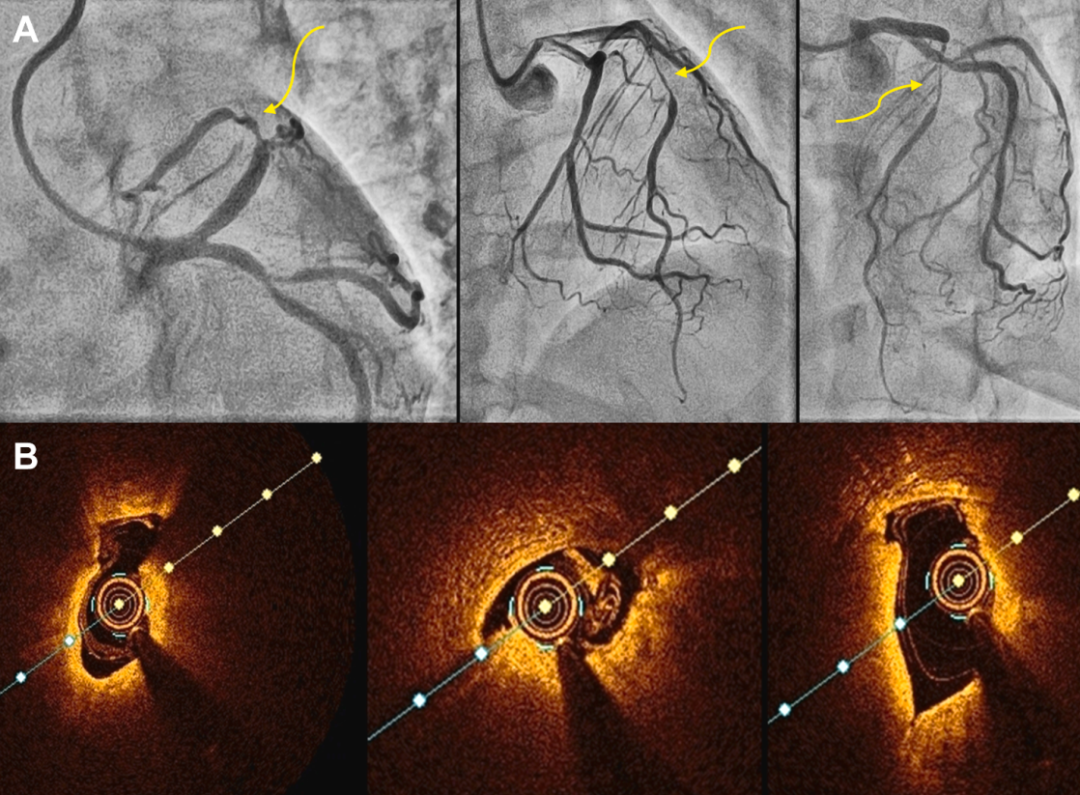

案例四:女性三支血管病变:造影提示LAD 存在SCAD,果真如此吗?

一位50岁女性,无合并症,表现为活动后呼吸困难、LVEF降低,造影提示三支血管病变,LAD疑似SCAD(图7A)。

图7 病例4:患者血管造影和左前降支(LAD) OCT 图像

(A)血管造影显示左前降支(LAD),提示管腔细薄呈管状,边缘锐利,高度怀疑为左前降支(LAD)的2A/3型 SCAD。(B)OCT 显示纤维钙化斑块,最小管腔面积为0.89mm2,无提示 SCAD 的特征。

她此前已在两个不同的医疗中心就诊,因症状持续来到本院。造影复查强烈提示LAD存在SCAD、RCA远端和钝缘支闭塞。然而,OCT(图7B)检查发现在造影上不可见的LAD纤维钙化病变,并未显示任何SCAD特征。随后,采用切割球囊对病变进行预处理,成功为患者实施了血管成形术。